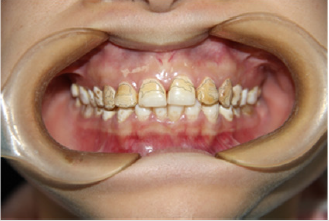

This study was approved by the local ethics and research committee (SYSEC-KY-KS-2018-030) and is registered in China Clinical Trials Registry (ChiCTR1800016630). The design of this RCT followed the guidelines published by the Consolidated Standards of Reporting Trials [9,10]. From January 2018 to August 2018, 72 patients with dental fluorosis at our Hospital were enrolled for the study. All patients signed informed consents. The inclusion criteria were as follows: age 18–50 years; diagnosis of fluorosis using the modified Dean’s index criteria with a range of 0 (normal), 0.5 (questionable), 1 (very mild), 2 (mild), 3 (moderate), and 4 (severe) [11]; fluorosis Dean’s grading 3 and 4; no dental caries and periodontitis; good oral and general health; no mental disorder; no large area filling and crown restorations; and patients’ informed consent for treatment. The exclusion criteria were as follows: pregnant and lactating women; allergy to test products; and structural cracks on the enamel surface. A total of 60 patients were enrolled according to the screening criteria. A blinded evaluator recorded the patient’s tooth staining using a digital camera (Canon EOS 600D, Tokyo, Japan) with a lens (Canon EF, 100mm) of the same shutter speed (1/200) and the aperture (F/11) in the indoor natural light. The camera was placed directly in front of the patient, and the lens was perpendicular to the maxillary incisor lip surface. The area of tooth staining and the total area of six maxillary anterior teeth were measured using image software (Figure 1).

A total of 60 patients were included in this study (Figure 2). The baseline characteristics of patients are shown in (Table 1). No significant difference was found in age (P = 0.534), gender ratio (P = 0.143) and Dean’s index (P = 0.557).

Before treatment, no significant difference was found between the two groups (P = 0.145). Both treatments reduced the area of fluoride staining (P < 0.001) (Table 2). The difference between the decrease in the fluoride staining area of the two groups was further compared. The decrease in the fluoride staining area was 7.355 (5.225,11.355) for group 1 and 4.08 (3.107,5.683) for group 2. Group 1 showed more improvement compared with group 2 (P < 0.001).

Visual Analog Scale 1: The two groups of patients thought that the treatment had improved fluoride staining. The patients in group 1 were more satisfied with the improvement in fluoride staining compared with the patients in group 2 (P < 0.001) (Table 3).